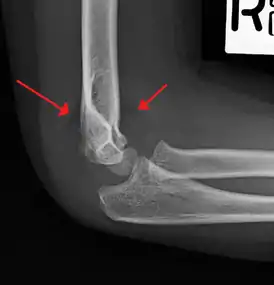

Malunion

The distal humerus grows slowly post fracture (only contributes 10 to 20% of the longitudinal growth of the humerus), therefore, there is a high rate of malunion if the supracondylar fracture is not corrected appropriately. Such malunion can result in cubitus varus deformity.